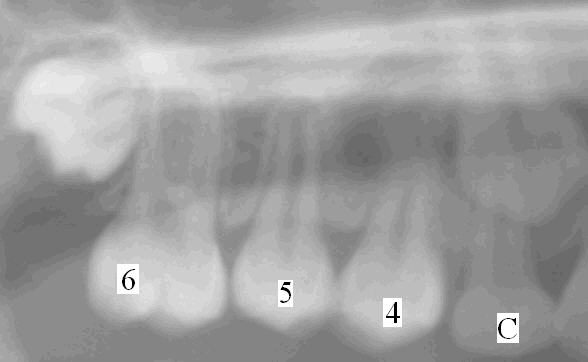

Today we report a case in which space regainer is used to fix minor dentition problem. One day a 9 year old girl came to my office with mom. Mom said, "One adult tooth comes out at a wrong place". Exam reveals that upper right adult 2nd premolar (5, Fig.2) erupts outside of (buccal to) normal dentition. Its predecessor (baby 2nd molar, E, Fig.1) has not fallen out. X-ray (Fig.1) shows that 1st premolar (4) tilts backward and blocks downward growth of 5. We feel it necessary to push 4 forward, i.e., to close the space between 4 and C (baby canine). First we extract E, take impression and make a model as shown in Fig.2. The latter shows that 5 is coming out initially outside (upper in the figure) of dentition.

Later the tooth #5 and neighboring teeth continue normal development. Fig.5 is X-ray taken 1 year after regainer removal. Compare Fig.1 and 5. Basically this girl does not need traditional braces for this area. Braces usually takes 1-3 years. Space regainer does not take that long, for this case, 7 weeks. Everything is made so simplified. Kids should brush very well no matter whether we need treatment or not.

Labels that have not been mentioned above are 3 and 7 (Fig.1). # 3 is adult canine which will replace C. #7 is adult 2nd molar which will erupts behind #6 without involvement of substitution (see lecture Space Maintenance).